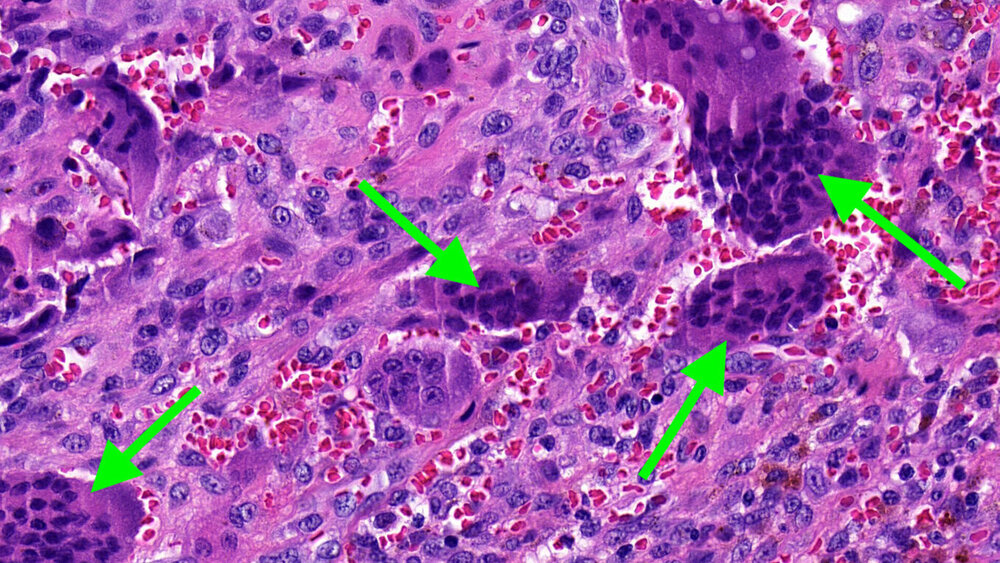

Zufallsbefund eines Riesenzelltumors bei langjähriger Bruxismus-Patientin